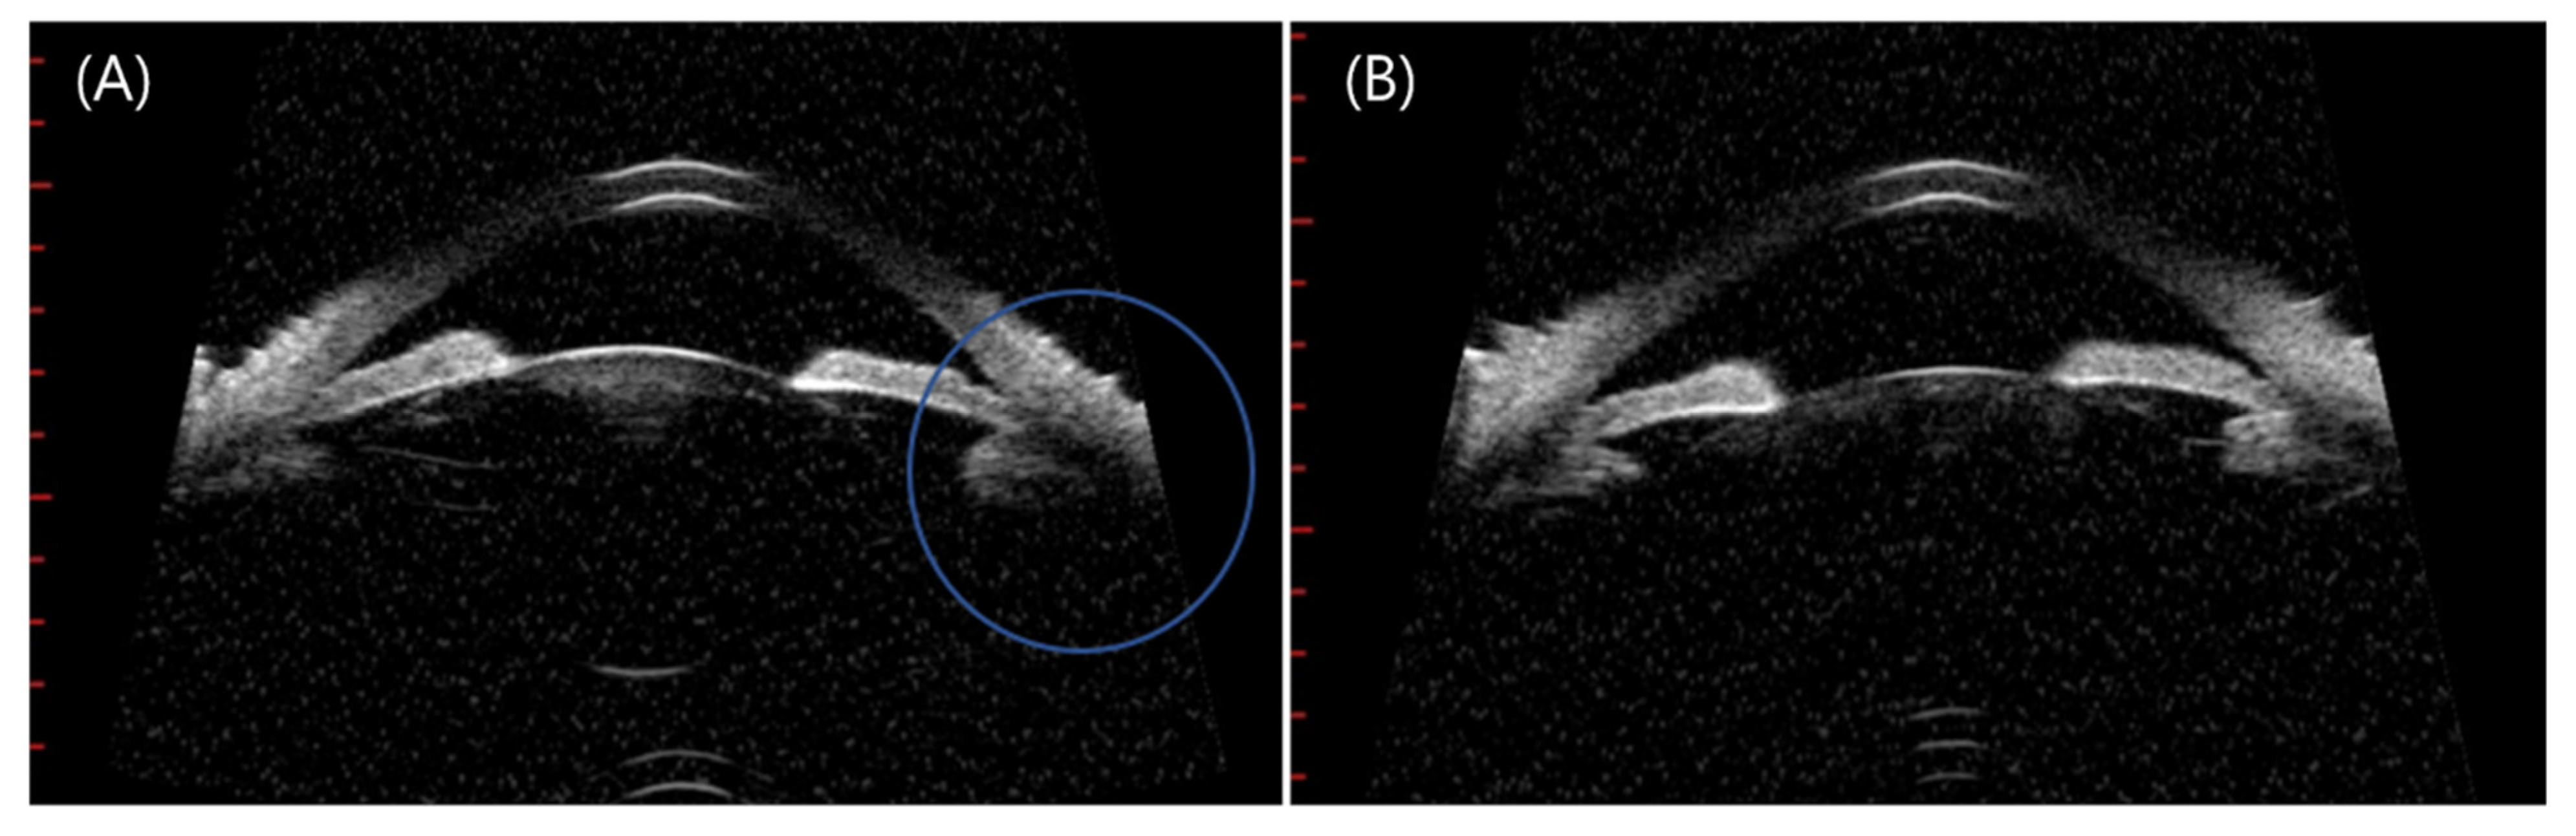

| 16 | 59 | F | AZD1222 | 1 | RE | 1 | 20/100 | 20/25 | ACG attack | HTN | ACG (2021) | Dorzolamide and timolol eyedrop | Phaco d |

| 17 | 64 | M | AZD1222 | 2 | RE | 6 | 20/50 | ACG with Lens displacement | None | None | None | Vitrectomy |